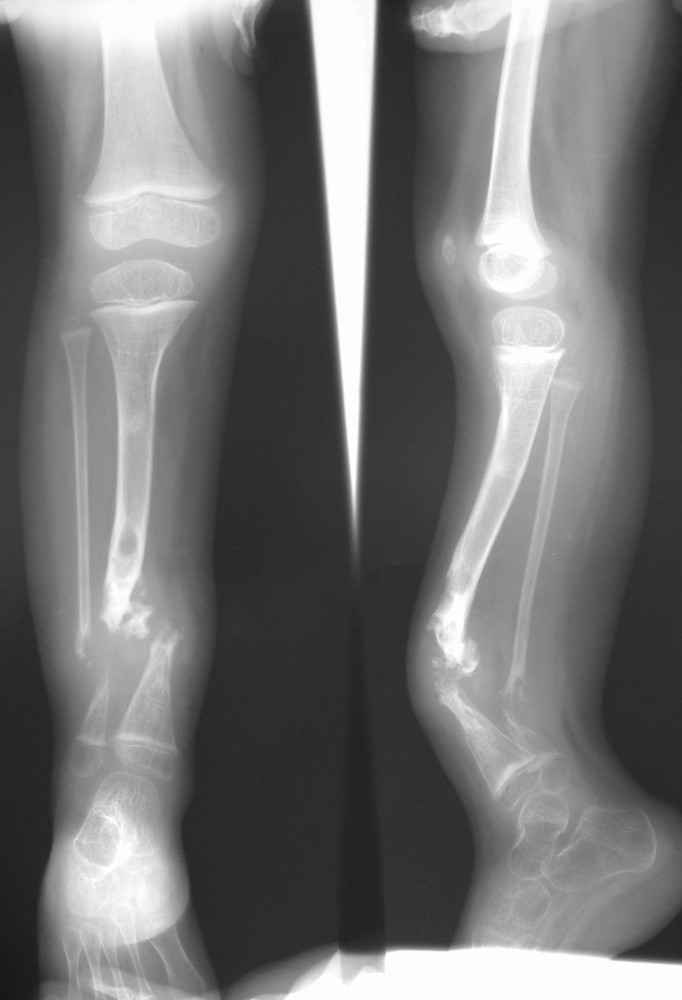

Врожденный псведоартроз после 3ей операции

Родилась от I беременности, протекавшей с анемией и носительством УПМФ, роды I срочные, осложненные.Дз: Врожденная аномалия правой голени, врожденный ложный сустав, врожденная дисплазия тазобедренных суставов, coxa valga. Нейрофиброматоз, факоматоз.

В 2006 г. - остеоклазия с иммобилизацией циркулярной гипосовой повязкой, в 2007 - интерлок, затем - костная аутопластика, стержневой АВФ.